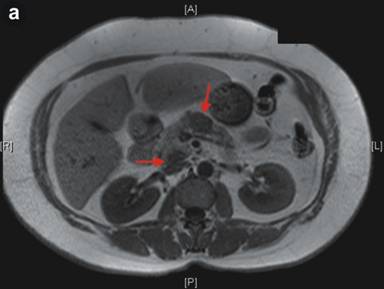

Reported herein is the case of a 60-year-old patient who was referred to our unit after an initial ultrasound scan for non-specific right upper quadrant pain identified a pancreatic mass. There was no significant past medical history or co-morbidities. Follow-up computed tomographic (CT) scan could not confirm the presence of the tumor; however, a repeat ultrasound scan showed a 2.7 cm mass within the body of the pancreas with a feeding arterial vessel into the lesion. Magnetic resonance imaging (MRI) confirmed a 2.3 cm lesion within the body of the pancreas and a further 1.8 cm lesion in the uncinate process (Figure 1a). These lesions demonstrated low signal on the T1-weighted images and an intermediate signal on the T2-weighted images. After the administration of radio-opaque contrast, the lesions enhanced to nearly the same degree as the adjacent normal pancreas, but appeared mildly hyperintense in the portal phase without any significant washout. Though the results were not completely characteristic of an adenocarcinoma, the suspicion of a neuroendocrine tumor (NET) was raised. Thereafter she was investigated with an endoscopic ultrasound (EUS). This revealed a round, 2 cm hypoechoic vascular lesion in the neck of the pancreas with clear margins, which was highly suspicious for a NET. In addition, two other lesions in the uncinate process and tail of the pancreas were identified, but did not have the classical characteristics of NETs. Next, a pancreatic protocol CT scan was organized, and surprisingly no focal enhancing lesion could be demonstrated. Only after using the previous MRI images as a guide, a 1.8 cm lesion was suggested within the body of the pancreas. The laboratory tests, including tumor markers and gut hormones, were all within the normal limits. A total pancreatectomy with splenectomy was performed based on the localization of the lesions.

Figure 1. a. Magnetic resonance imaging (MRI) demonstrates two lesions (red arrows: 1.8 cm diameter in uncinate process and 2.3 cm diameter in body of pancreas) which are homogeneously hypo-intensive (T1-weighted sequence). b. Hematoxylin and eosin stained section from the nodule in the body of pancreas reveals an area of nodular lymphoid hyperplasia consisting of several hyperplastic lymphoid follicles with large germinal centers of varying sizes (white arrows) within the pancreatic parenchyma (original magnification x20). c. Higher magnification showing reactive germinal center (gc) with tingible body macrophages with well-preserved mantle zone (mz) and adjacent exocrine pancreatic parenchyma. Pathological diagnosis was pancreatic nodular lymphoid hyperplasia previously called “pseudolymphoma” (hematoxylin and eosin staining; original magnification x100). |